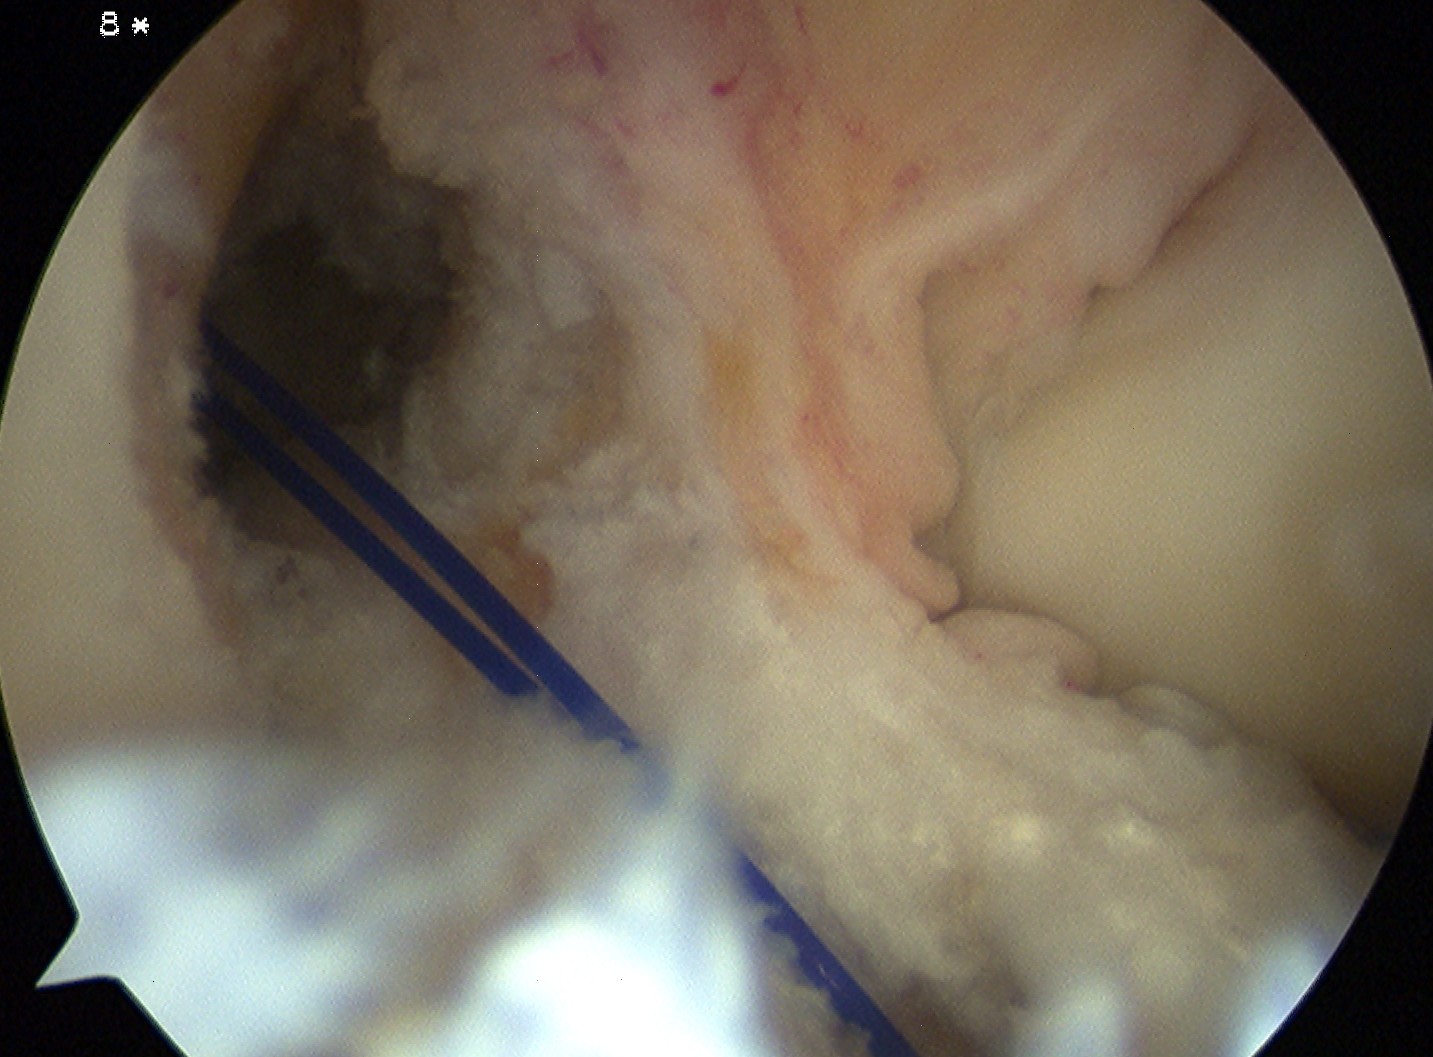

Femoral tunnel

Entry Point

- 1.30 o'clock on R, 10.30 o'clock on L

- 6 mm offset guide through anteromedial portal

- aim to leave 2 mm posterior wall

Femoral tunnel beath pin

- hyperflex knee, pass beath pin

- if don't hyperflex, tunnel can be very long

- want wire to emerge anterior to lateral intermuscular septum

- if tunnel too vertical, can emerge in PFJ